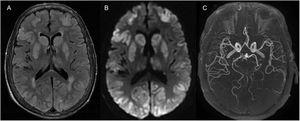

A 70-year-old woman with a history of chronic obstructive pulmonary disease, hypertension, and heart failure was transferred to our hospital after an episode of witnessed out-of-hospital cardiac arrest, for which she received 20min of cardiopulmonary resuscitation. At admission, she was comatose, requiring intubation. Neurological examination showed an absence of brainstem reflexes without any pharmacological influence. Twelve hours later, a magnetic resonance imaging (MRI) of the brain (Fig. 1) showed extensive bilateral, cortical–subcortical and basal ganglia hyperintensities on the fluid-attenuated inversion recovery sequence (A) with restricted diffusion (B) and normal arterial blood supply (C); findings consistent with hypoxic–ischemic brain injury (HIBI). The patient died 48h after admission. The current guidelines for HIBI suggest performing a brain MRI 2–5 days after the event, however recent data shows that the diffusion-weighted imaging (DWI) sequence on an MRI can predict neurological outcomes as early as 3h after this catastrophic event.